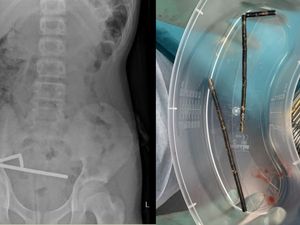

Dokter di Selandia Baru terpaksa mengeluarkan sebagian usus seorang remaja laki-laki berusia 13 tahun. Ini disebabkan adanya 100 magnet yang bersarang di usus.